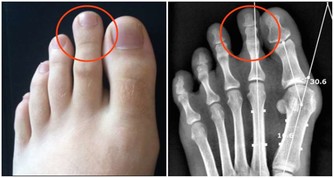

2、勤護腎臟

高尿酸除了傷害關節外,也會連累心血管系統和腎臟,因此應積極控制尿酸,其含量不能超過360微摩爾。少吃或不吃高嘌呤食物,多喝白開水,堅持運動來降低尿酸濃度;同時應定期做腎臟B超、腎功能檢查,用於評估腎臟是否健康。